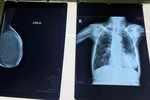

Để hưởng ứng phong trào tháng chống căn bệnh ung thư vú, chính quyền thành phố Paris đã chiếu sáng tháp Eiffel - một hành động như để lan tỏa những thông điệp hữu ích cho cộng đồng.

Để hưởng ứng phong trào tháng chống căn bệnh ung thư vú, chính quyền thành phố Paris đã chiếu sáng tháp Eiffel-một hành động như để lan tỏa những thông điệp hữu ích cho cộng đồng./.